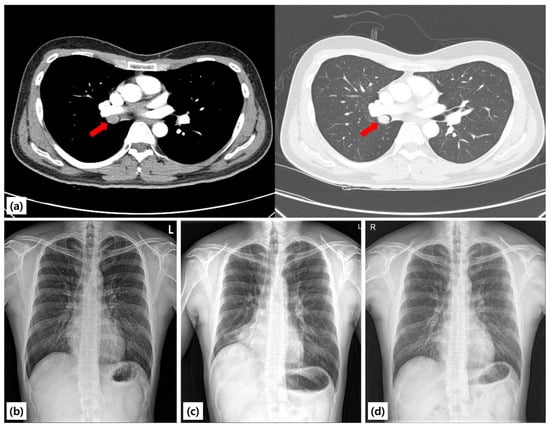

Background and Clinical Significance: Endobronchial leiomyoma is a rare benign tumor of the respiratory tract, accounting for less than 2% of all benign pulmonary neoplasms. Most cases have been treated surgically or with endoscopic modalities such as laser or rigid bronchoscopy-assisted cryotherapy. Flexible bronchoscopic cryoextraction has been rarely reported, typically with 2.2-mm probes. Small-caliber cryoprobes (1.1- and 1.7-mm) have been validated for diagnostic transbronchial cryobiopsy but not for therapeutic removal of leiomyoma. We report a case of complete removal of endobronchial leiomyoma using a 1.7-mm cryoprobe via flexible bronchoscopy, demonstrating full airway and physiologic recovery. Case Presentation: A 25-year-old never-smoking man was referred after an abnormal health-screening chest radiograph demonstrated right middle and lower lobe atelectasis. Chest CT revealed a mass obstructing the proximal bronchus intermedius. Spirometry showed reduced FEV1 and FVC with preserved FEV1/FVC ratio, consistent with central airway obstruction. Therapeutic flexible bronchoscopy (Olympus BF-1TQ290) was performed under endotracheal intubation. Initial forceps biopsies were followed by transbronchial cryobiopsy with a 1.7-mm cryoprobe, applied for five freeze–adhesion cycles. The mass detached en bloc and was retrieved without complications, resulting in complete airway recanalization and visualization of the right middle and lower lobe bronchi. Histopathology showed interlacing fascicles of bland spindle cells with cigar-shaped nuclei, positive for SMA and desmin and negative for S-100 and CD34, confirming leiomyoma. The patient was discharged the next day. At one-year follow-up, bronchoscopy and CT demonstrated no recurrence, and spirometry normalized. Conclusions: Reports combining flexible bronchoscopy with a 1.7-mm small-caliber cryoprobe for en bloc removal of endobronchial leiomyoma are rare. This technique may represent a minimally invasive option for selected cases, provided careful hemostatic planning and appropriate case selection. Full article

Figure 1